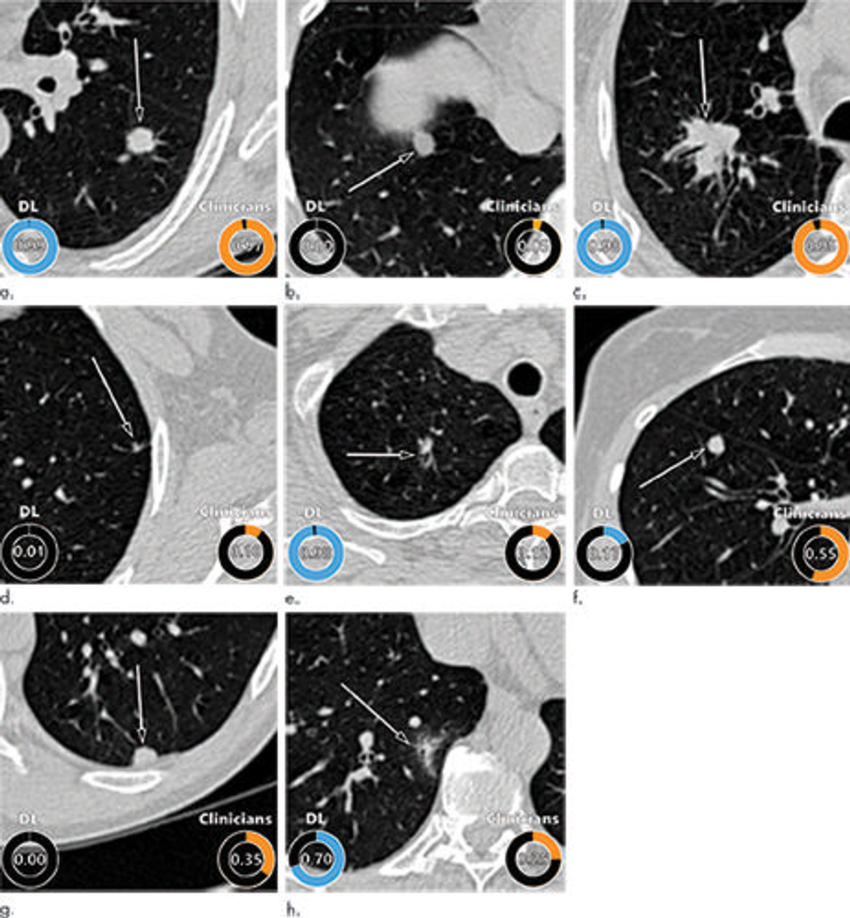

Figure 5. Examples of CT images in nodules from the Danish Lung Cancer Screening Trial (DLCST) with (a–d) high and (e–h) low agreement between the deep learning (DL) algorithm and the clinicians for malignancy risk estimation. Numbers in rings on bottom left of each image are the algorithm’s malignancy score, and numbers in rings on bottom right of each image are the clinicians’ median malignancy score. The extent of the color filling is proportional to the malignancy risk (on a scale of 0 to 1, where 0 represents the lowest risk and 1 represents the highest risk). (a) Image shows a 15-mm spiculated and lobulated malignant nodule (arrow) classified correctly by the DL algorithm and clinicians. (b) Image shows an 11-mm smooth benign nodule (arrow) classified correctly by the DL algorithm and clinicians. (c) Image shows a 29-mm benign lesion (arrow) suspected to be a malignant nodule by both the DL algorithm and clinicians. This participant was diagnosed with pneumonia at clinical workup. (d) Image shows a 5-mm malignant nodule (arrow) called benign by both the DL algorithm and clinicians. The growth of the nodule can be seen from follow-up CT examinations. (e) Image shows a 15-mm part-solid malignant nodule (arrow) classified correctly by the DL algorithm and not suspected to be malignant by seven of 11 clinicians. (f) Image shows an 8-mm benign nodule (arrow) predicted to be moderately suspicious by the clinicians and called benign by the DL algorithm. (g) Image shows an 11-mm malignant nodule (arrow) predicted to be moderately suspicious by most clinicians but called benign by the DL algorithm. (h) Image shows a 16-mm benign lesion (arrow) classified correctly by the clinicians and predicted to be highly suspicious by the DL algorithm.